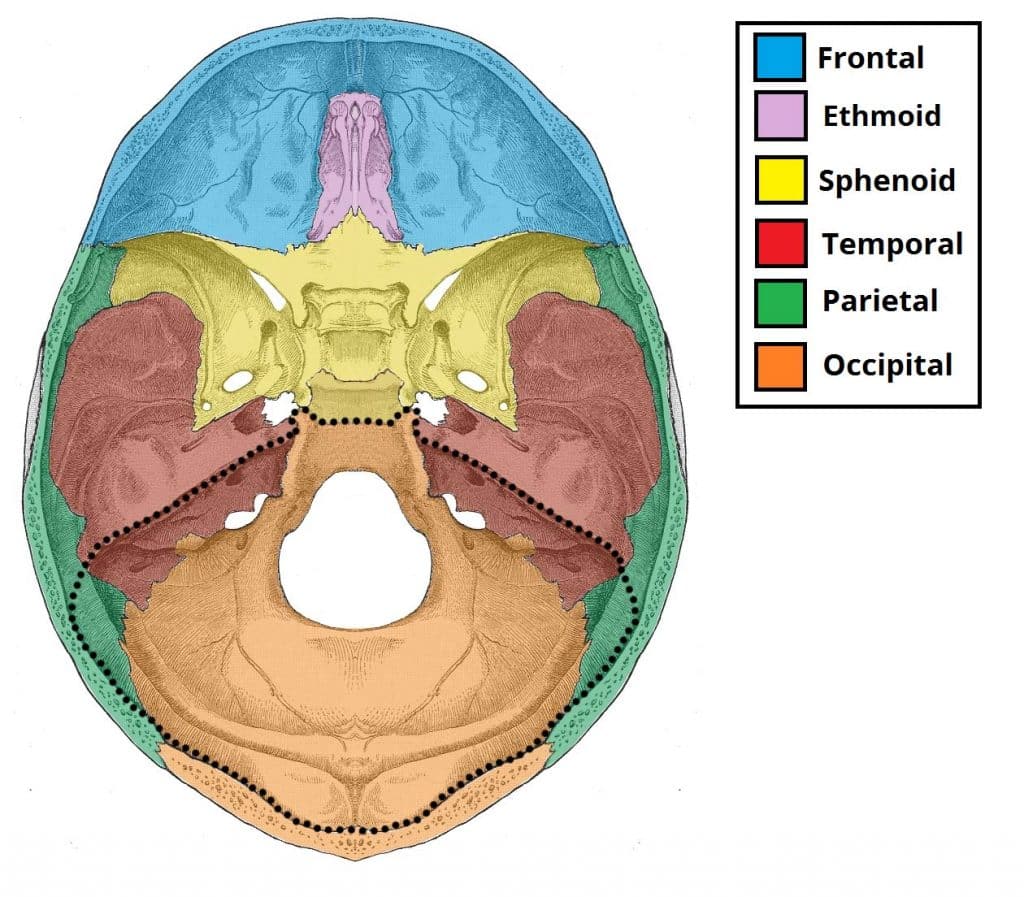

The floor of the cranial cavity is divided into three distinct depressions. They are known as the anterior cranial fossa, middle cranial fossa and posterior cranial fossa. Each fossa accommodates a different part of the brain. The posterior cranial fossa is the most posterior and deep of the three cranial fossae. It accommodates the brainstem and cerebellum. In this article, we shall look at the borders, contents and clinical correlations of the posterior cranial fossa. Pro Feature - 3D Model You've Discovered a Pro Feature Access our 3D Model Library Explore, cut, dissect, annotate and manipulate our 3D models to visualise anatomy in a dynamic, interactive way. Learn More Borders The posterior cranial fossa is comprised of three bones: the occipital bone and the two temporal bones. It is bounded as follows: Anteromedial – dorsum sellae of the sphenoid bone (large projection of bone superiorly that arises from the body of the sphenoid). Anterolateral – superior border of the petrous part of the temporal bone. Posterior – internal surface of the squamous part of the occipital bone. Floor – mastoid part of the temporal bone and the squamous, condylar and basilar parts of the occipital bone. By TeachMeSeries Ltd (2025) Fig 1The bones of the cranial floor. The posterior cranial fossa has been outlined.Fig 1.0 – The bones of the cranial floor. The posterior cranial fossa has been outlined. Contents The posterior cranial fossa houses the brainstem and cerebellum. The brainstem is comprised of the medulla oblogata, pons and midbrain and continues down through the foramen magnum to become the spinal cord. The cerebellum has an important role in co-ordination and fine motor control – more information here. Alongside the gross anatomical structures of the brainstem and cerebellum, the posterior cranial fossa also accommodates associated arteries and nerves. Some key structures will be discussed with regards to their foramina below. Foramina There are several bony landmarks and foramina present in the posterior cranial fossa (a foramen is simply a hole that allows the passage of a structure – usually a blood vessel or nerve). Temporal Bone The internal acoustic meatus is an oval opening in the posterior aspect of the petrous part of the temporal bone. It transmits the facial nerve (CN VII), vestibulocochlear nerve (CN VIII) and labyrinthine artery. Occipital Bone A large opening, the foramen magnum, lies centrally in the floor of the posterior cranial fossa. It is the largest foramen in the skull. It transmits the medulla of the brain, meninges, vertebral arteries, spinal accessory nerve (ascending), dural veins and anterior and posterior spinal arteries. Anteriorly an incline, known as the clivus, connects the foramen magnum with the dorsum sellae. The jugular foramina are situated either side of the foramen magnum. Each transmits the glossopharyngeal nerve, vagus nerve, spinal accessory nerve (descending), internal jugular vein, inferior petrosal sinus, sigmoid sinus and meningeal branches of the ascending pharyngeal and occipital arteries. Immediately superior to the anterolateral margin of the foramen magnum is the hypoglossal canal. It transmits the hypoglossal nerve through the occipital bone. Posterolaterally to the foramen magnum lies the cerebellar fossae. These are bilateral depressions that house the cerebellum. They are divided medially by a ridge of bone, the internal occipital crest. By TeachMeSeries Ltd (2025) Fig 2The bony landmarks and foramina of the posterior cranial fossa. Clinical Relevance Cerebellar Tonsillar Herniation Cerebellar tonsillar herniation is the downward displacement of the cerebellar tonsils through the foramen magnum. It is also known as ‘coning’. It is produced by a raised intracranial pressure, which has a varied aetiology. Causes include hydrocephalus, space occupying lesions, and a malformed posterior cranial fossa. Cerebellar tonsillar herniation results in the compression of the pons and medulla, which contain the cardiac and respiratory centres. Thus, a herniation of this type ultimately results in death from cardiorespiratory arrest. By Basket of Puppies (Own work) [CC-BY-SA-3.0] via Wikimedia Commons Fig 3Sagittal MRI imaging of the head, demonstrating cerebellar tonsil herniation. Do you think you’re ready? Take the quiz below Pro Feature - Quiz The Posterior Cranial Fossa Question 1 of 3 Submitting... Skip Next Rate question: You scored 0% Skipped: 0/3 1800 More Questions Available Upgrade to TeachMeAnatomy Pro Challenge yourself with over 1800 multiple-choice questions to reinforce learning Learn More Rate This Article